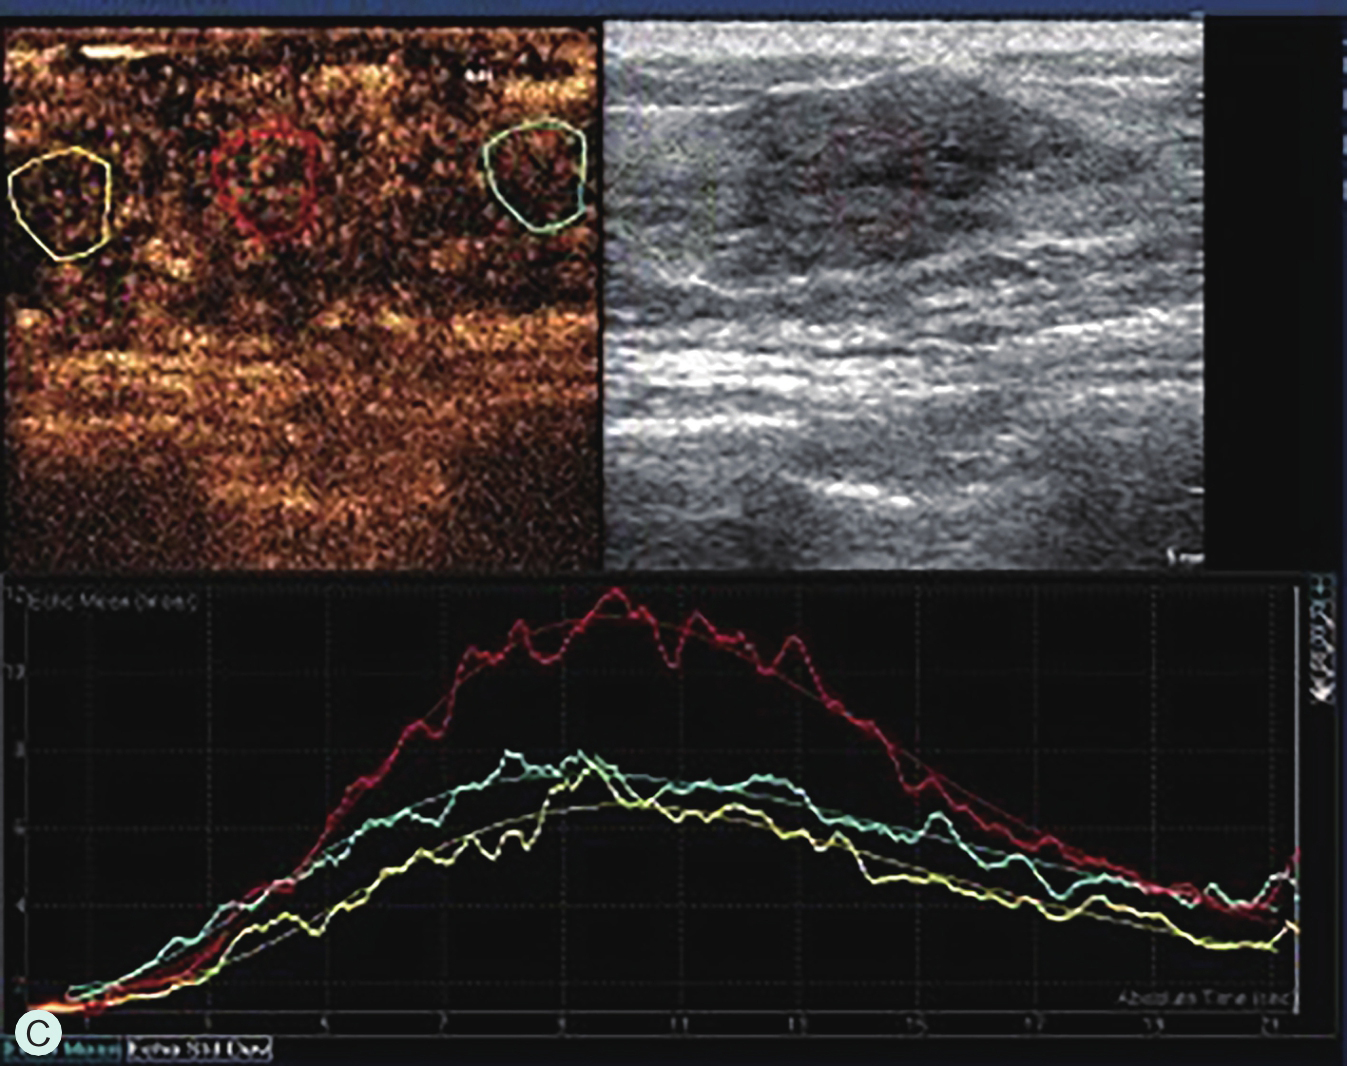

图2-2-1 确定造影病灶

A.病灶二维图像;B、C.病灶CDFI图像;D.同侧腋窝淋巴结情况;E.病灶弹性成像图像

A.同步测量病灶大小与高增强范围;B.勾勒病灶与增强范围;C.定量分析

图2-2-11 乳腺肿瘤的微血管演进示意图

6.定量分析时,对不同区域分别取样,或包络整个病灶取样,所获得的时间-强度曲线参数也会出现差异,故取样时应尽可能包络病灶最大范围,并在病灶内及正常腺体以相同的感兴趣区面积多点取样进行相互比较,取样时应避开首先增强的滋养血管或无增强区,定量分析作为定性分析的辅助工具,应基于定性分析判读结果综合分析。